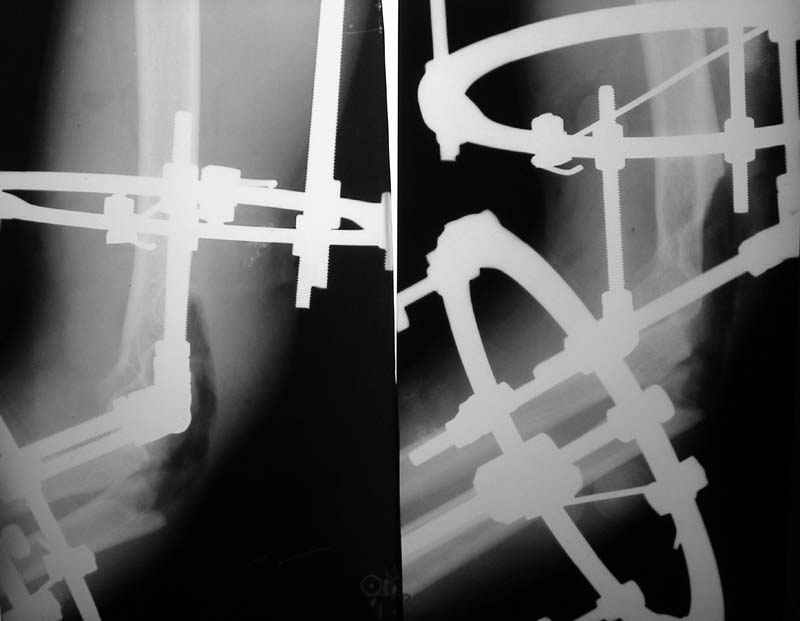

Операция - ПХО, ЧКО АВФ (см.приложение).

Репонировать фрагменты локтевой и плечевой кости не представилось возможным (по сути <каша> из мелких осколков сомнительной жизнеспособности), резекция головки лучевой кости, иссекли мягкие ткани, кожа зашита почти без натяжения, дренажи, АВФ.

Мнения? Рекомендации? Сформировать ложный сустав?